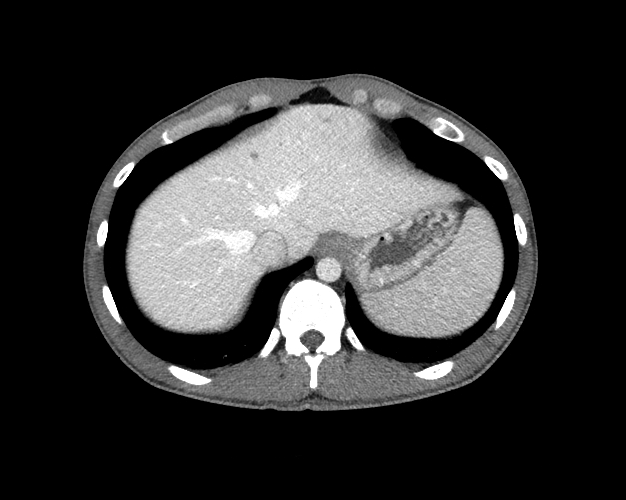

Body

Covers abdominal CT anatomy.